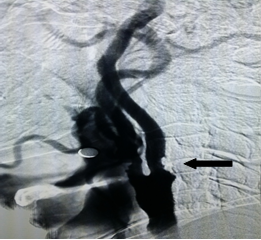

医生为患者实施右侧颈内动脉狭窄支架置入术治疗(CAS),术后脑DSA显示:造影后狭窄处明显改善,颅内血管供血有改善(图四)。

术前DSA(图三) 术后DSA(图四)